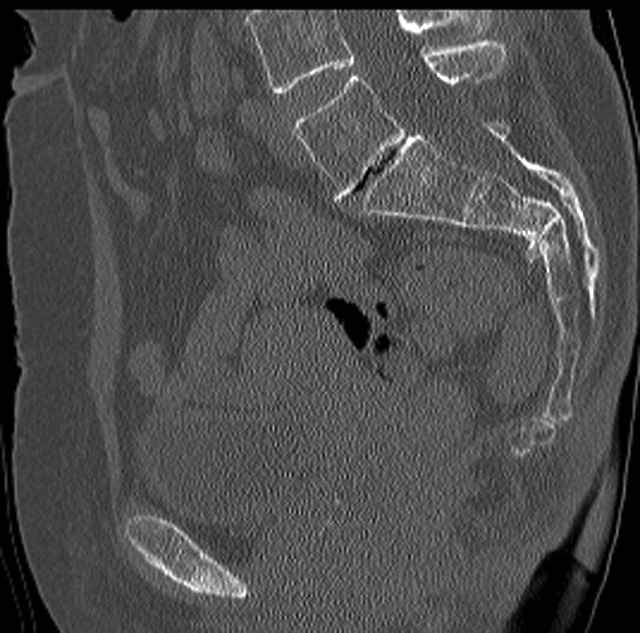

Percutaneous Fixation

(B) Ramus-Retrograde

2 TransIliac-TransSacral

Upper Segment